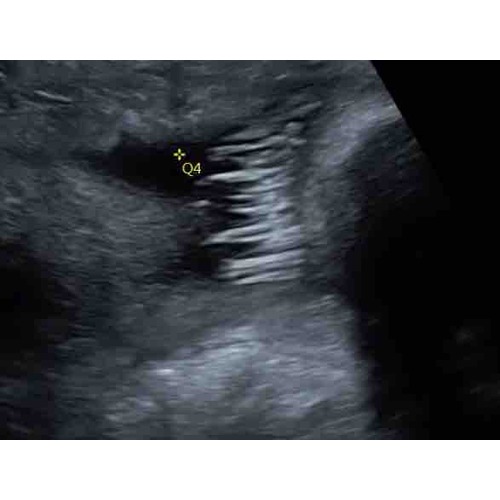

Beetje haar gezien met 31 weken ze vertelde dat het vanaf dan pas echt gaat groeien nu maandag 35 weken ben benieuwd straks volgende week een echo misschien kunnen we dan wat meer zien.

Bij ons zag je het toevallig ook op de echo van 36 weken. Dat zag er echt h ...

Bij ons zag je met 26w al heel veel haar, super leuk 😍 ben ook benieuwd ha ...

Ja hier met 29 weken al haar te zien! Ondertussen bijna 39 week dus kom er snel genoeg achter hoop ik, wat voor haardos ze heeft 😂